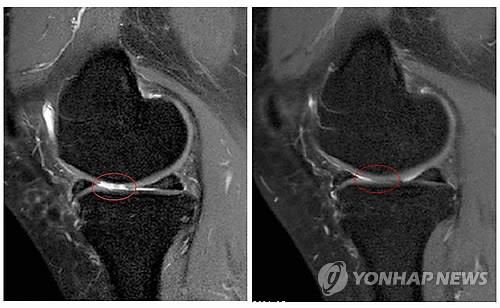

(서울=연합뉴스) 한성간 기자 = 자신의 지방조직에서 채취한 자가지방세포 이식이 퇴행성 관절염 치료에 효과가 있다는 연구결과가 나왔다.

세포치료·면역요법 국제컨소시엄(International Consortium for Cell Therapy and Immunotherapy)의 야로슬라프 미할레크 박사는 자가지방세포 이식이 퇴행성 관절염의 증상을 완화하고 손상된 관절을 일부 회복시키는 효과가 있다는 임상시험 결과를 발표했다고 의학뉴스 포털 메디컬익스프레스(MedicalXpress)가 16일 보도했다.

퇴행성 관절염 남녀환자 1천114명(평균연령 62세)을 대상으로 진행된 임상시험에서 각자에게서 떼어낸 지방조직 샘플에서 기질혈관분획(SVF)세포를 채취, 손상된 관절에 이식하고 12~54개월 동안 지켜본 결과 이 같은 효과가 나타났다고 마할레크 박사는 밝혔다.

환자들은 치료 후 3~12개월에 걸쳐 점차 증상이 호전됐으며 이렇다할 부작용은 없었다.

12개월 후 질병활성도가 50% 이상 호전된 환자는 91%에 이르렀다. 63%는 질병활성도가 75% 이상 개선됐다.